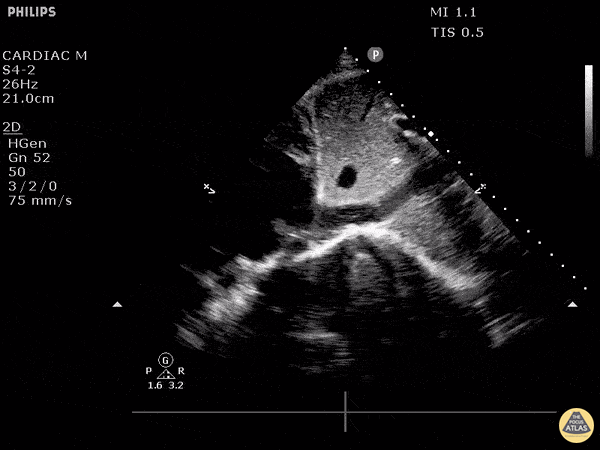

IVC & Abnormal Venous Waveforms - Clot At Junction of Right Atrium and IVC

This patient initially presented post-operatively to the emergency department with complaints of dyspnea. As we fan through this saggital view of the IVC as it enters the right atrium, we can see hyperechoic structures suggestive of clot formation. An alternative view of this clot from a subxiphoid view can be seen here. The patient was subsequently diagnosed with a DVT that extended into their central femoral vein, at the same leg that was recently operated on. Image courtesy of Robert Jones DO, FACEP @RJonesSonoEM Director, Emergency Ultrasound; MetroHealth Medical Center; Professor, Case Western Reserve Medical School, Cleveland, OH View his original post here